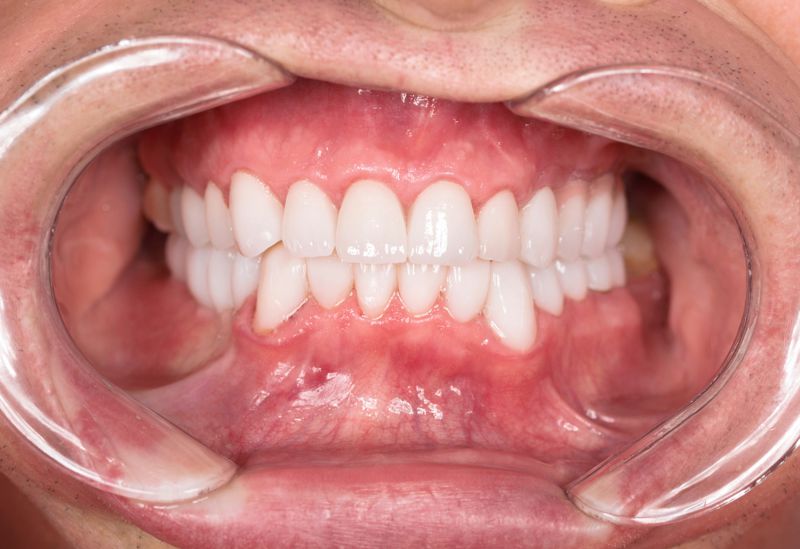

Samodzielna korona nie obciążająca zębów sąsiednich - to dzisiaj możliwe.

+ brak konieczności szlifowania zębów

+ brak zalegania resztek pokarmowych pod mostem

Wszczepienie implantu na ogół jest zabiegiem bezbolesnym i nie wymagającym dłuższej rekonwalescencji.